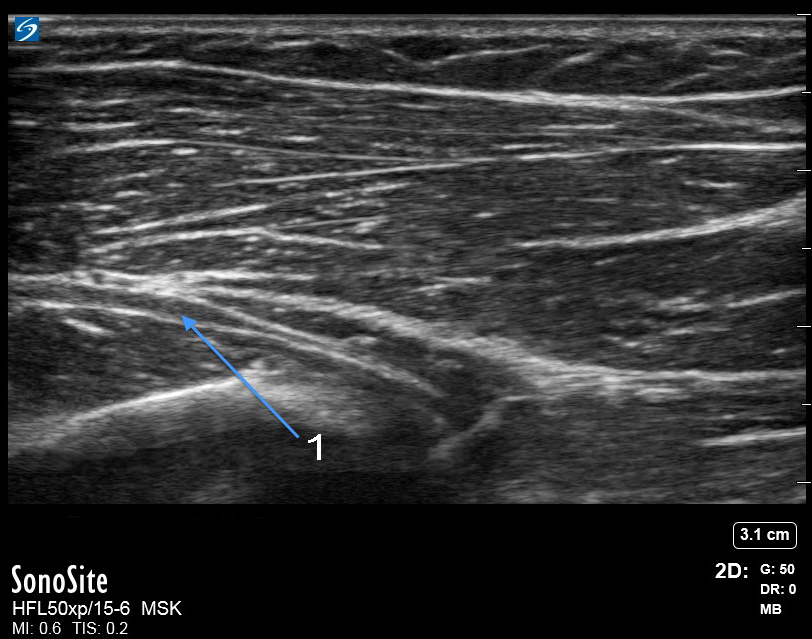

肘部后骨间神经长轴图像

右 - 长轴

后骨间神经